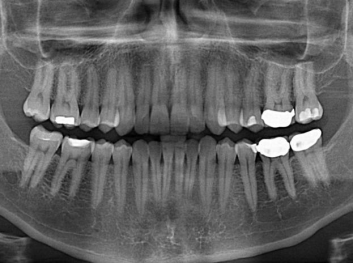

Adam Celiz,是來自諾丁漢大學的研究人員,他和同事開發(fā)的這種新型合成生物材料,能刺激干細胞在牙髓部的生長。與普通材料一樣,這種合成材料被填充到牙齒并用UV光硬化。

在體外測試中,材料刺激干細胞進入牙本質(zhì)的增殖和分化速度,促進形成牙齒骨組織。研究人員認為,一旦材料在受損牙齒中應(yīng)用,這些干細胞可以自動修復(fù)來自填充物上的損壞。在本質(zhì)上,該生物材料將使牙齒自愈。